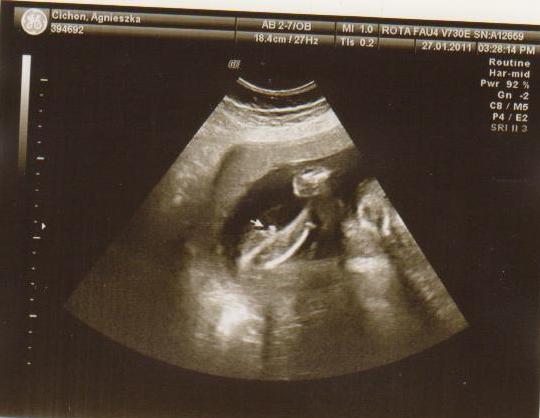

wklejam tylko zdjecia Mateuszka Tichonka na jej prośbe :-)

9a.jpg3a.JPG4a.JPG5a.jpg8a.JPG2a.JPG6a.jpg7a.JPG1a.jpg